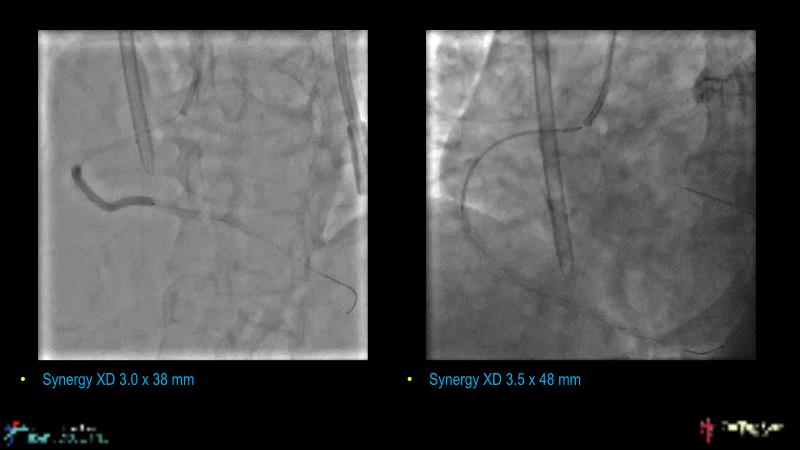

With this session, keep up to date on the evidence, trials and outcome data for intravascular lithotripsy in severely calcified lesions. Learn how to use this technique in real-world patients and understand its role in the treatment algorithm for severely calcified coronary lesions.

- To learn how to use intravascular lithotripsy in real-world patients with severely calcified coronary lesions

- To understand the appropriate role of intravascular lithotripsy in the treatment algorithm for severely calcified lesions